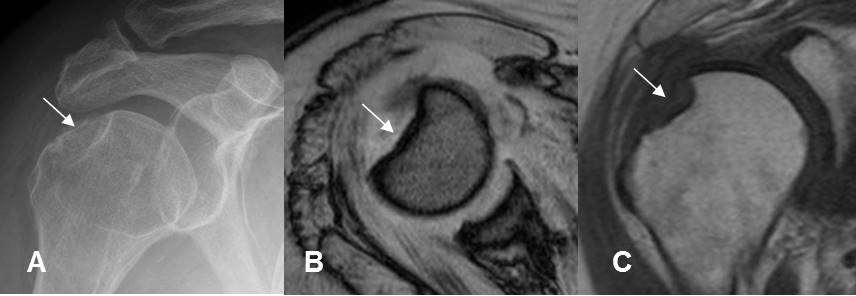

Fig 189. Fractura de Hill Sachs.

A: Rx AP, B: RM axial en FFE y C: RM coronal en T1. Zona deprimida en la parte superoexterna de la cabeza del húmero, por fractura de Hill Sachs.